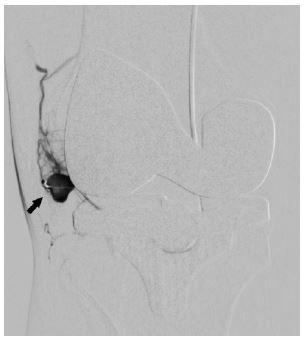

In view of continued knee joint swelling, the patient underwent right lower limb angiography the following week through the right femoral artery approach which identified a Pseudoaneurysm arising from the inferior medial genicular artery. This was embolized using 250 microns’ particles- embospheres and 2mm push able coils. Selective angiogram performed from superior medial and lateral genicular artery showed abnormal blush and pruning was done using 250-micron embospheres (Figures 3,4 & 5). An Ice pack was placed over the knee while instilling embolic agent particles to cause vasoconstriction of the skin arterial supply to avoid ischemia.

Figure 4: Post-operative Anteroposterior and lateral radiographs of Knee showing total knee replacement in place and gross joint eff usion in form of loss supra and infra patellar fat pad.